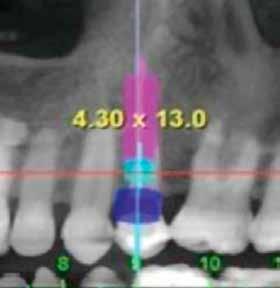

Cikkünkben összesen négy, kétrészes kerámiaimplantátum klinikai és radiológiai eredményeit mutatjuk be, amelyeket a felső, moláris régióba helyeztünk be.

A műtéti tervezéshez mindkét esetben CBCT-felvételt használtunk, majd az utánkövetési időszakban periapikális röntgenfelvételekkel ellenőriztük az implantátumokat. A fogeltávolítást követően azonnali implantáció történt, az alveolus fala és az implantátum felszíne közt fennmaradó réseket csontpótlóval töltöttük ki. A három hónapos gyógyulás leteltével az ideiglenes koronákat eltávolítottuk, A-szilikonnal lenyomatot vettünk, majd három lítium-diszilikát és egy monolitikus cirkónium-dioxid korona készült. A páciensek utánkövetése mindkét esetben minimum tizenkét hónap volt, amelynek során valamennyi implantátumot klinikailag és radiológiailag is sikeresnek ítéltünk az osszeointegráció, a marginális csont stabilitása és a periimplantáris szövetek egészsége tekintetében.

2. a–c ábrák: Kiindulási CBCT-felvételek.

lantátum 4,3 mm átmérőjű és 13 mm hosszúságú volt. A behajtási nyomaték mind a négy esetben 35–40 Ncm tartományban volt, amely lehetővé tette az azonnali terhelést. Tizenkét hónap elteltével egyik implantátumnál sem tapasztaltunk csontfelszívódást, a kemény- és a lágyszövetek stabilitása kielégítő volt.